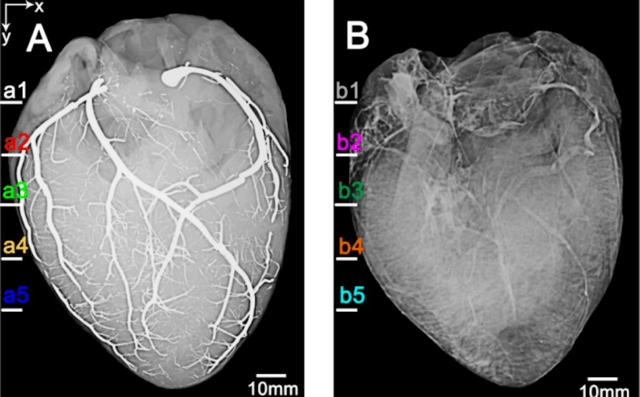

It may surprise you that, despite our seemingly vast knowledge of the human body, were still decently in the dark when it comes to the smaller portions of the cardiovascular system. Even more surprising, the answer to that problem isnt lying in more powerful microscopes. Its in a heart pumping pure, shiny liquid metal.Until now, modern imaging techniques have given us a fantastic understanding of the hearts larger blood vessels, but theyve done little to give us a clear view of the innumerable smaller branches these vessels break into. As we stand today, one of the most widely used imaging methods involves filling the vessels with a contrast agent typically iodine that absorbs x-rays more than the tissue around it, resulting in an image in which the vessels themselves are very much apparent; the denser the contrast agent, the clearer the image. The only problem is that our current contrast agents carried a pretty limited rate of x-ray absorption—until now, that is.

via These Are the First Ever Images of a Heart Injected With Liquid Metal.